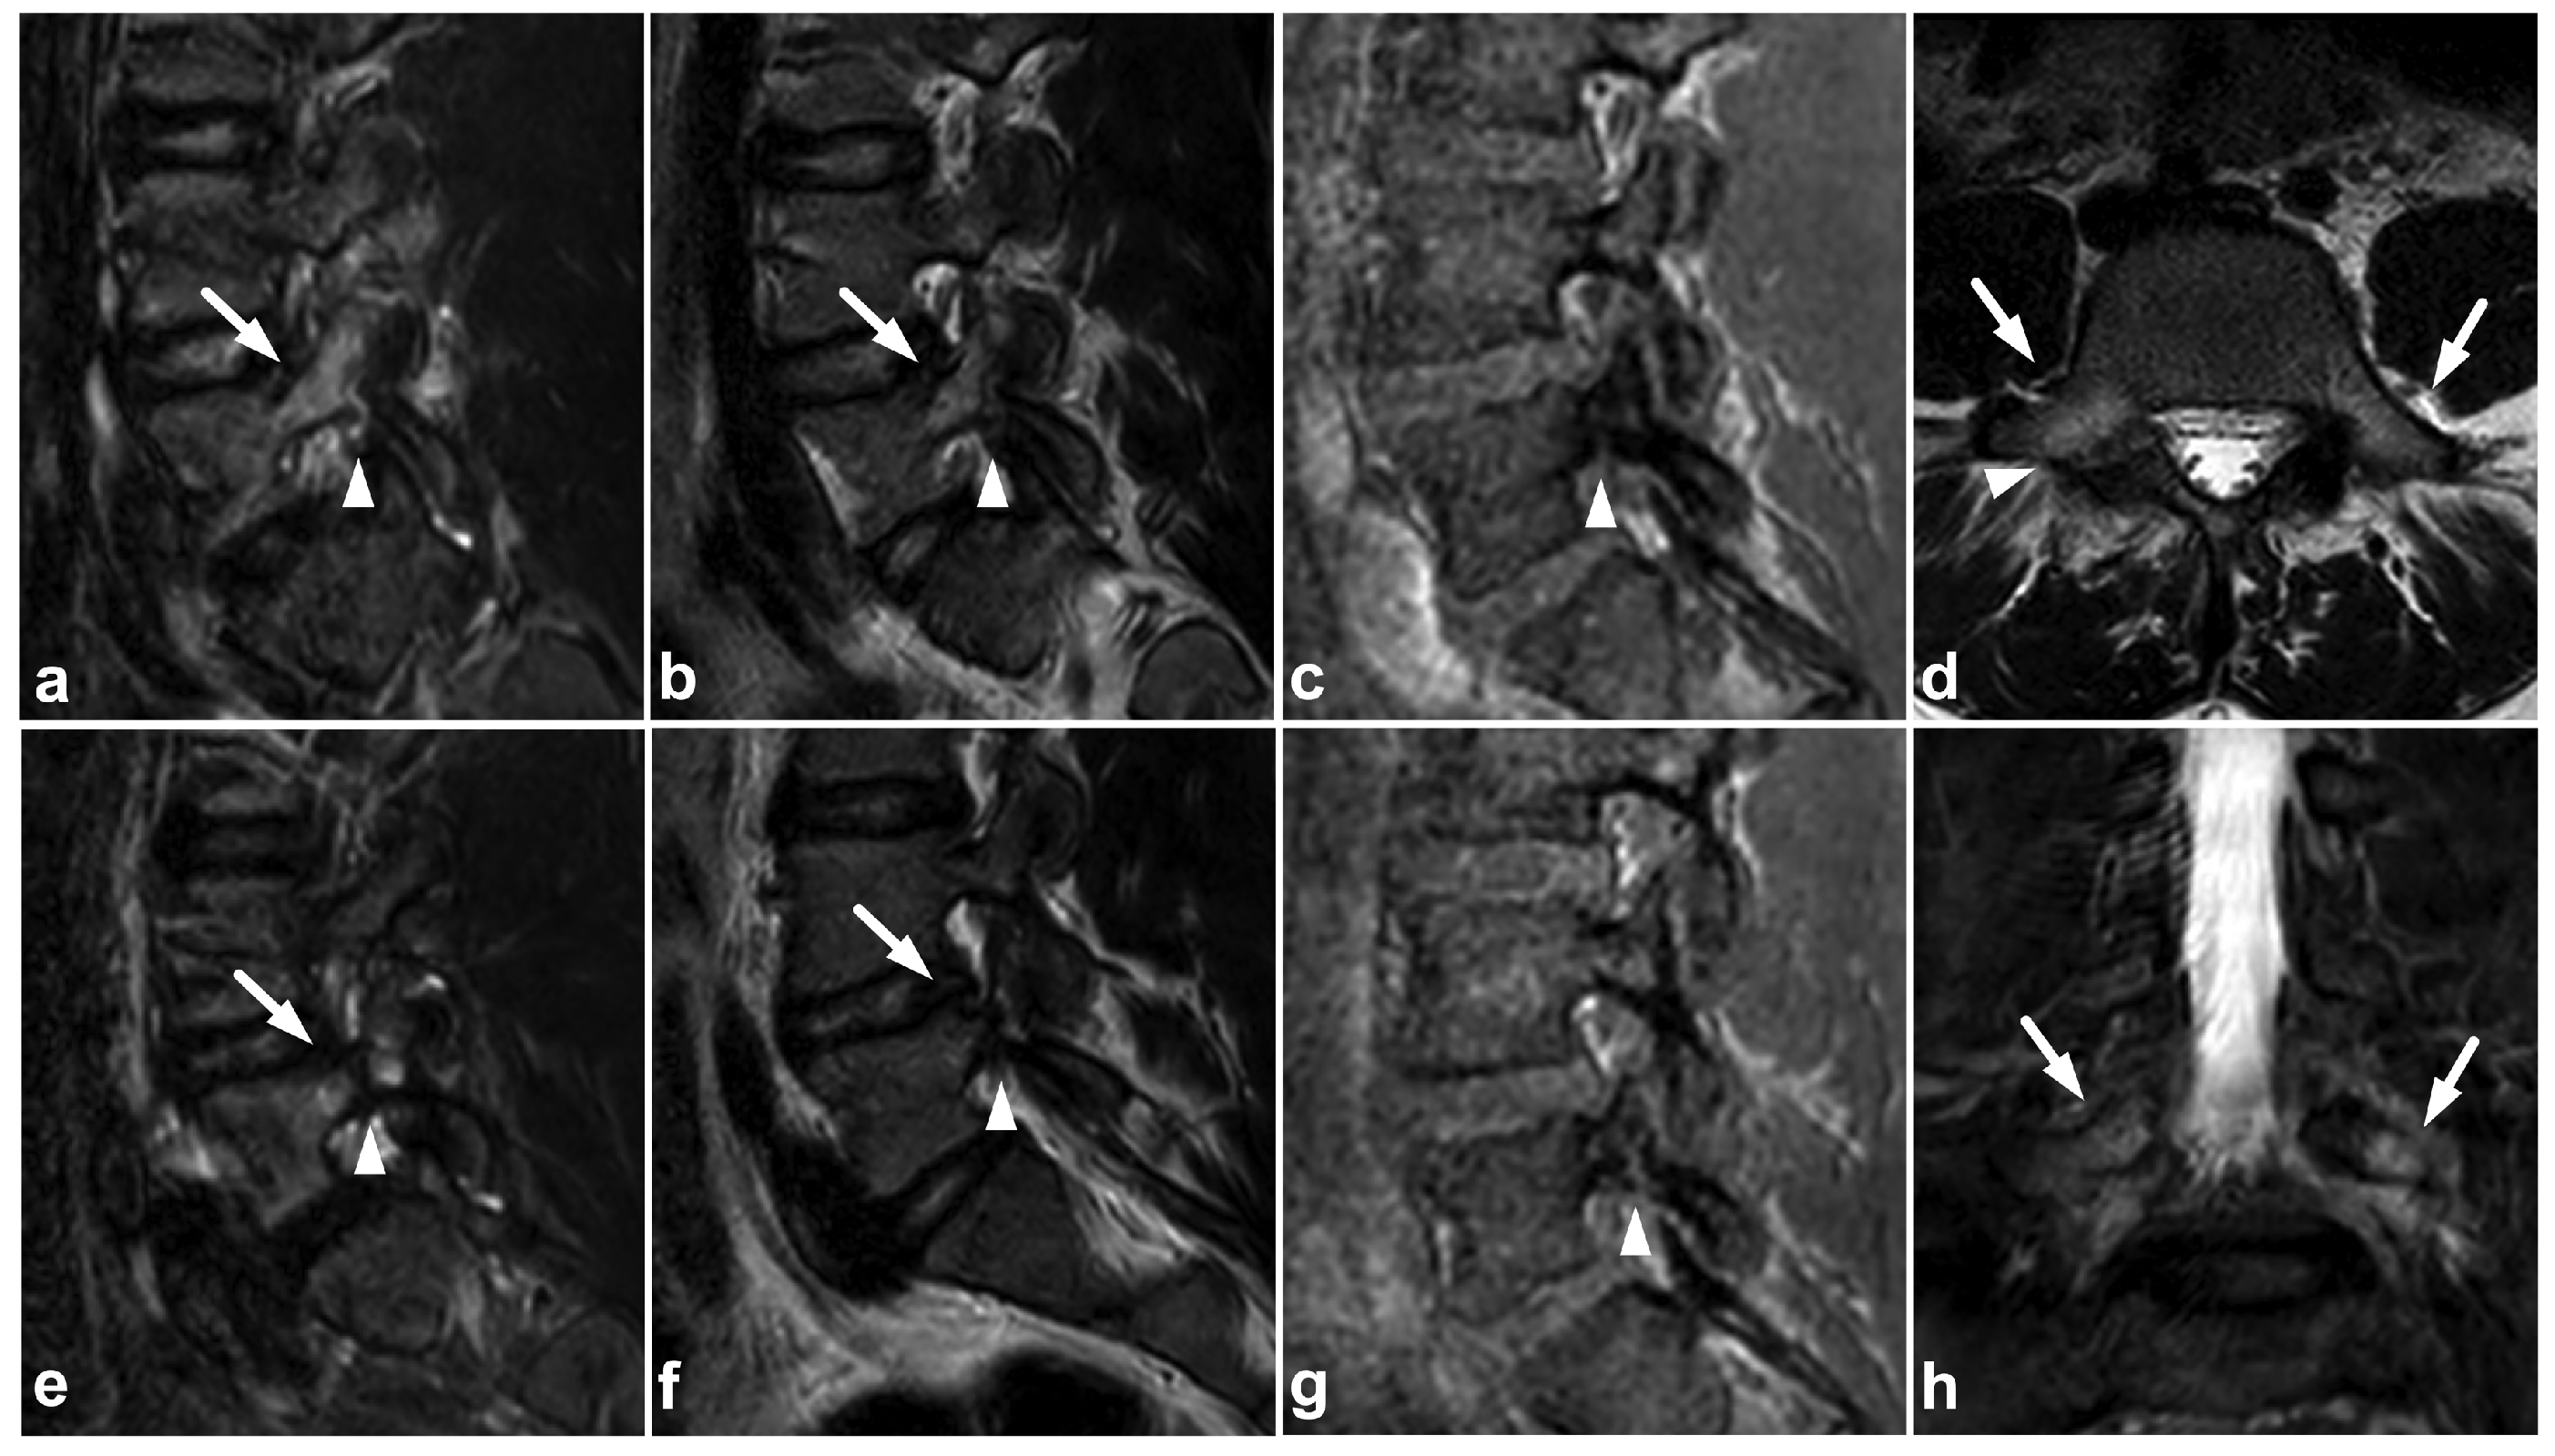

4.2. Posterior Ligament Complex

4.3. Anterior and Posterior Longitudinal Ligaments